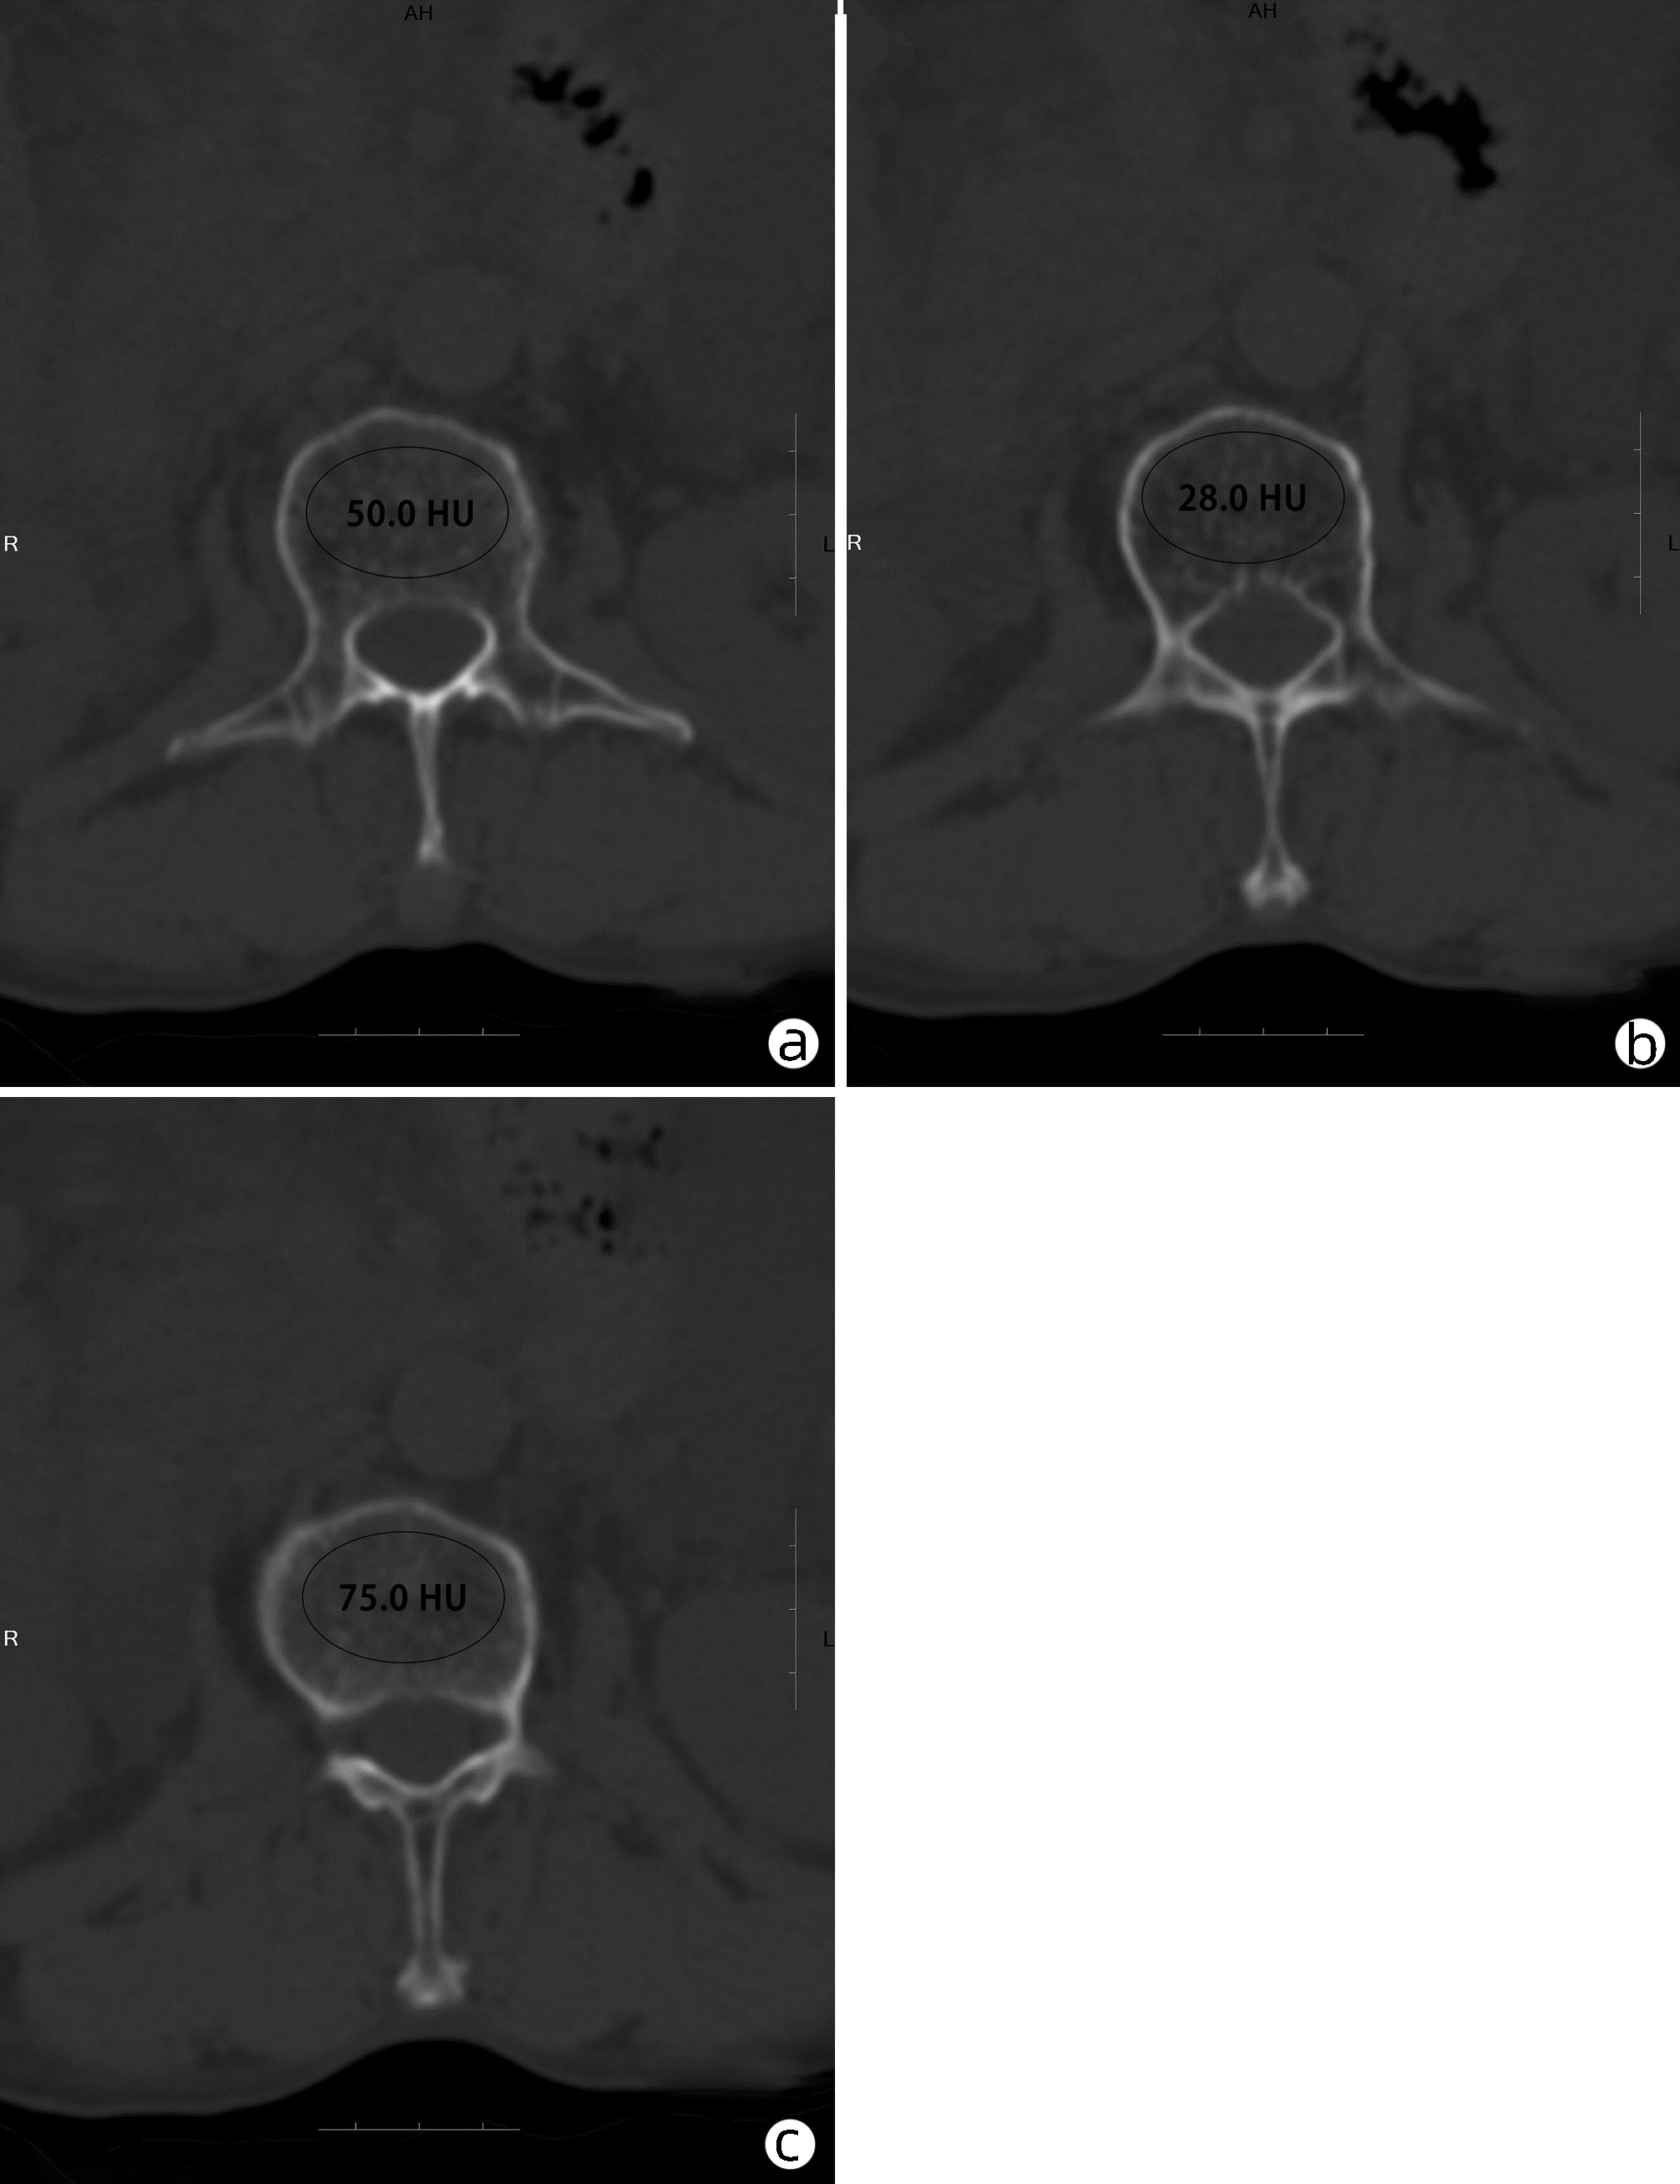

慢性乙型肝炎患者骨量减少/骨质疏松的危险因素及CT值的诊断价值

张静怡, 唐映梅, 李嘉琦, 王倩, 张宸瑞

2022, 38(5): 1041-1047. DOI: 10.3969/j.issn.1001-5256.2022.05.013

摘要(1220) HTML (508) PDF (2526KB)(83)

摘要:

目的  评价在慢性乙型肝炎患者腹部CT中通过测量胸、腰椎CT值,诊断骨量减少/骨质疏松的诊断价值。分析慢性乙型肝炎患者发生骨量减少/骨质疏松的危险因素。  方法  回顾性纳入2019年1月—2020年12月在昆明医科大学第二附属医院就诊的慢性乙型肝炎患者112例,所有患者均完善了腹部CT检查,部分患者完善了双能X线骨密度测定(DXA)。测量T12椎体至L3椎体的CT值,分析每一椎体CT值与DXA检查基于L1~L4椎体测得的T-score值相比诊断骨量减少/骨质疏松的诊断价值。以椎体CT值为诊断标准,将纳入的慢性乙型肝炎患者分为骨量减少/骨质疏松组(n=55)与骨量正常组(n=57),对比两组患者临床特征、生化指标,分析慢性乙型肝炎患者发生骨量减少/骨质疏松的危险因素。符合正态分布的计量资料两组间比较采用t检验;非正态分布的计量资料两组间比较采用Mann-Whitney U检验。计数资料组间比较采用χ2检验、Fisher确切检验、Bonferroni校正检验。相关性采用Pearson相关分析。多因素分析采用二元logistic回归分析。根据受试者工作特征曲线(ROC曲线)评估T12~L3椎体CT值诊断慢性乙型肝炎患者合并骨量减少/骨质疏松的诊断价值。一致性检验采用Kappa检验。  结果  分析46例在同次住院中完善了腹部CT和DXA检查患者的T12~L3椎体CT值,均分别与DXA检查结果中基于L1~L4椎体计算的T-score值有显著正相关性(rT12=0.694,rL1=0.661,rL2=0.781,rL3=0.685,P值均<0.001);经ROC曲线分析,L2椎体CT值ROC曲线下面积最大(0.863),诊断骨量减少/骨质疏松具有较好准确性,与DXA检查结果具有较好一致性(K=0.648,P<0.001)。分析112例慢性乙型肝炎患者临床特征、生化指标,提示高龄(比值比为1.108,95%CI:1.026~1.196,P=0.009)、合并肌少症(比值比为2.788,95%CI:1.009~7.707,P=0.048) 是骨量减少/骨质疏松发生的危险因素。  结论  慢性乙型肝炎患者常需定期复查腹部CT评估肝脏疾病进展情况,通过测量患者腹部CT图像中L2椎体CT值、L3椎体层面骨骼肌面积筛查是否存在骨量减少/骨质疏松、肌少症,及时干预,提高患者的预后、生活质量,具有较高临床意义。